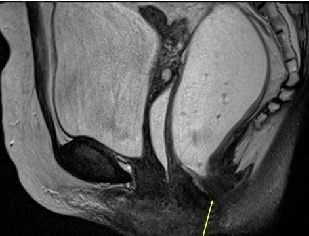

Исследование у больных с нарушениями дефекации: обструкция на выходе, дисфункция тазового дна, пролапс прямой кишки или органов таза, скопление рентгеноконтрастных меток в дистальных отделах при исследовании времени транзита по толстой кишке. Введение рентгеноконтрастной пасты с вязкостью, более близкой к вязкости стула, чем обычного контраста. Исследование со статическими снимками или видеодефекография во время опорожнения кишечника больным сидя на туалетном кресле. Оценка включает в себя динамическое наблюдение, структурные и функциональные изменения процесса дефекации и ее полноты.

Нормальная последовательность: правильное расположение аноректального отдела - над лобково-копчиковой линией; тонус лобково-прямокишечной мышцы обеспечивает тракцию кпереди с формированием аноректального угла (норма: 90-100° в покое); удерживание содержимого приводит к элевации тазового дна и уменьшению аноректального угла; напротив, натуживание приводит к увеличению аноректального угла (релаксация иуборектальной мышцы), возникновению эвакуаторных сил, раскрытию анального канала и полной эвакуации.

Аноректальный угол при дефекографии в покое и при натуживании.

а) Цель. При доступности, МРТ - предпочтительное исследование, поскольку позволяет визуализировать изменения внутри и вне просвета прямой кишки в течение всего времени опорожнения. В противоположность «динамической МРТ» (в положении больного лежа на спине), открытая интервенционная МРТ дефекография позволяет исследовать больного в естественном положении сидя во время естественного опорожнения кишечника.